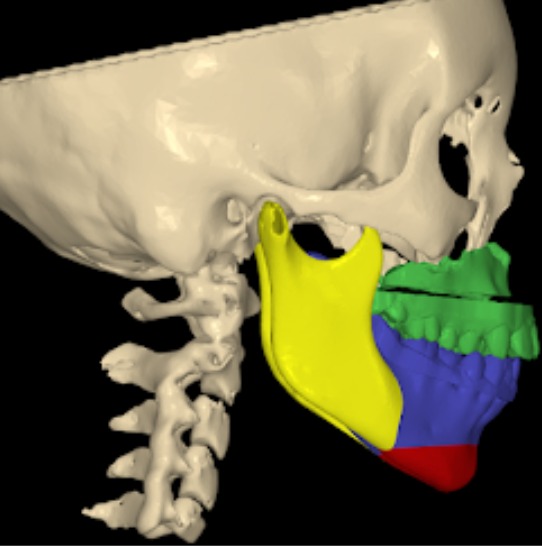

Maxillary prognathism is a dental and facial condition in which the upper jaw extends forward more than normal in relation to the lower jaw. This condition can affect the overall balance of the face and may lead to difficulties with proper bite alignment, chewing, and speech. In many cases, maxillary prognathism develops due to genetic factors, abnormal jaw growth, or developmental conditions that affect the structure of the facial bones.

Le Fort Osteotomy Procedures

- Le Fort I Osteotomy: A procedure that separates the upper jaw from the rest of the facial bones, which facilitates repositioning it forward, backward, superiorly (upward), or inferiorly (downward), thereby creating a better facial appearance.

- Le Fort II Osteotomy: Mainly performed on the midface and cheekbones for a "sunken" or depressed skeletal complex in the midface area.

- Le Fort I Augmentation: A procedure that involves the forward movement of the maxilla (upper jaw), thereby repositioning it to correct a depressed upper jaw problem.

- Pre-surgical Orthodontics: Often needed before the actual surgery takes place. Imaging: X-rays and CT scans are required.

- Planning: Virtual surgical planning is performed on a computer, along with model surgery.